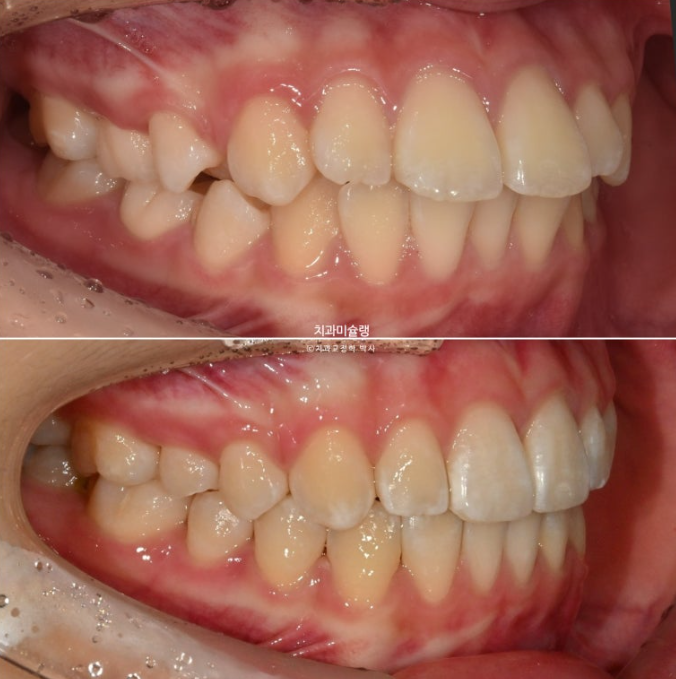

측면에서 보면 뻗쳐서 튀어나와있죠

앞니돌출은 개선이 되었습니다.

1급 물샐틈 없는 교합관계를 보입니다.

24.04~25.11

앞니 돌출과 높낮이 차이를 개선하고 약간의 치간삭제를 더해 치료했으므로 이제 더이상 앞니가 토끼이같이 커보이지 않습니다.